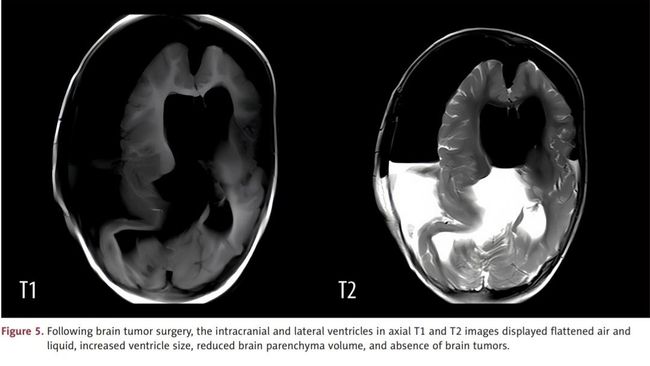

Dokter melakukan MRI pada kepalanya dan menemukan adanya massa berdiameter 13 cm di tengkoraknya. Dalam massa tersebut, terlihat adanya bongkahan tulang yang panjang.

Pada titik ini, dokter memutuskan melakukan operasi untuk mencoba menghilangkan massa tersebut. Mereka menidurkan anak tersebut dan melakukan kraniotomi, menghilangkan sebagian tengkoraknya.